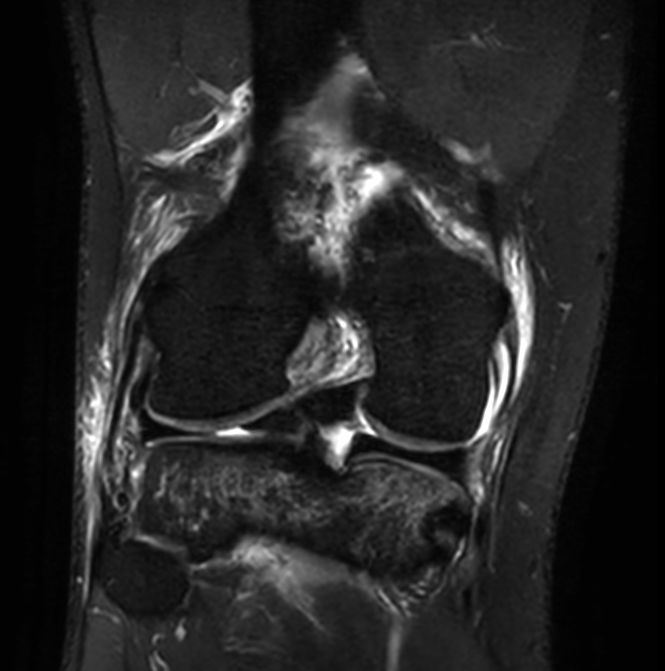

3D PDw TSE FatSat (coronal reformat)